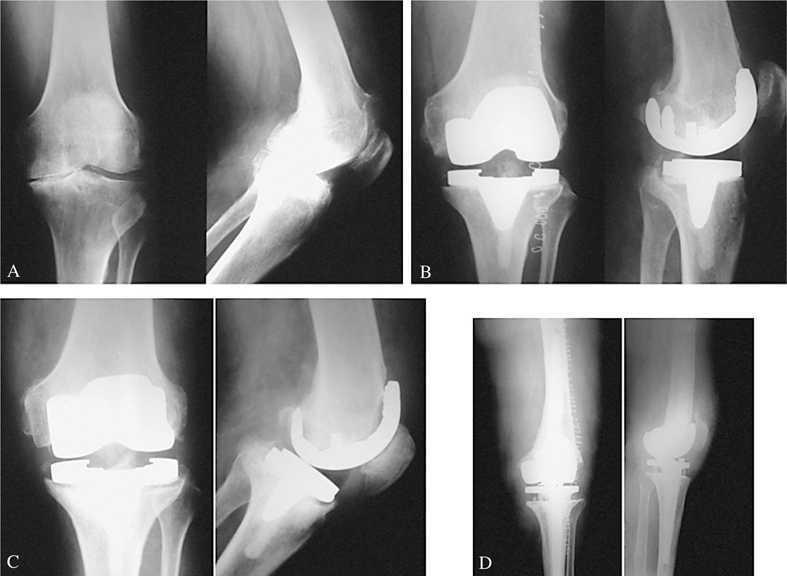

Dentro del apartado de complicaciones, encontramos (tabla 3): 5 casos de infecciones superficiales (5,4%) que se solucionaron con medidas físicas, curas locales y antibioterapia oral; 7 de movilización aséptica (7,6%) --6 pacientes-- (uno de ellos fue bilateral), que precisaron cirugía de revisión posteriormente (fig. 4); 2 de infección profunda precoz (2,2%), que se solucionaron con lavados artroscópicos y antibioterapia intravenosa; 2 de infección profunda tardía (2,17%), uno precisó rescate de la ATR en dos tiempos (fig. 5) y el otro mejoró con lavado artroscópico y antibioteraapia intravenosa; 4 de dehiscencia de la sutura (4,3%), uno de ellos precisó consultar con el servicio de cirugía plástica; 3 de trombosis venosa profunda (TVP) --uno de ellos se complicó con un tromboembolismo pulmonar (TEP)--, que mejoraron con el tratamiento adecuado; 9 presentaron dolor en la cara anterior de la rodilla (9,8%) y 3 tendinopatía de la pata de ganso (3,3%); 2 de fractura periprotésica de fémur, una fue intraoperatoria y se solucionó cementando el componente femoral y reposo de la pierna y el otro fue a los 8 años de la intervención --tras una caída-- que se resolvió con un clavo endomedular retrógrado estático (fig. 6). No observamos ningún caso de desgaste o luxación del polietileno (0%), ni complicaciones neurológicas. En las figuras 4 a 8 mostramos algunos casos clínicos de esta serie.

Figura 4.(A) Mujer de 71 años (54/50 puntos). (B) Malposición del componente tibial en el postoperatorio. (C) Movilización aséptica del componente tibial a los dos años que precisó recambio protésico (24/15 puntos).

Figura 5.(A) Varón de 67 años (20/20 puntos). (B) Control radiográfico postoperatorio satisfactorio consiguiendo 7° de valgo. (C) Movilización séptica a los tres años, que precisó recambio en dos tiempos e implantación de prótesis rotacional (D).

Figura 6.(A) Mujer de 69 años con fractura periprotésica que fue resuelta con clavo intramedular retrógrado. (B) Buen resultado clínico (50/70 puntos).

Figura 7.(A) Mujer de 53 años (38/42 puntos). (B) Radiografía postoperatoria satisfactoria. (C) Buen aspecto a los 3 años de evolución. (D) Resultado excelente a los 7 años de la intervención (90/80 puntos).